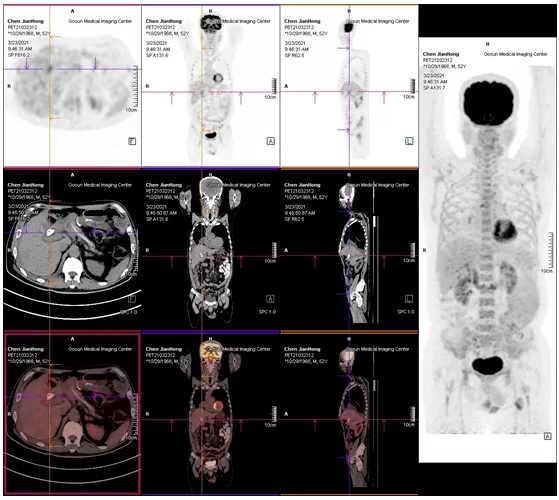

2021年05月 PET/CT檢查結果

復查PET-CT提示原術區(qū)復發(fā)病灶、肝內轉移灶、右側胸膜轉移灶控制良好

治療效果評估

用藥3個月后,患者精神狀態(tài)明顯好轉,食欲改善,體重增加,腫瘤指標下降,PET/CT結果提示,無明顯腫瘤復發(fā)或轉移征象,肝內腫瘤活性已受抑制。